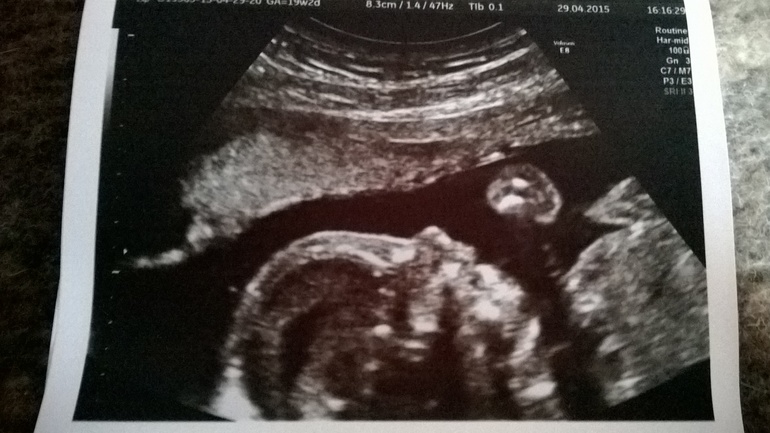

Фотопуз:

А вот наш Максим Дмитриевич (пока так. Как родится - посмотрим как лучше назвать )